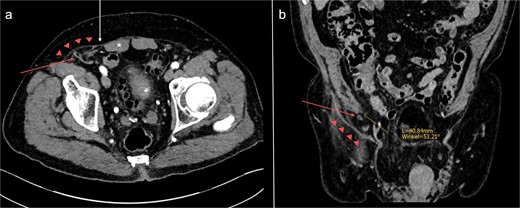

For this reason, incarcerated SpH was initially considered the patient’s primary diagnosis. However, previous CT-studies and intraoperative findings indicated that the hernia was not situated within the Spigelian aponeurosis. It had formed directly through the transversus abdominis and internal oblique muscles, ⁓4 cm superolateral to the internal inguinal ring, away from the myopectineal orifice (Fig. 4). Therefore, the defect does not comply with the definitions of Spigelian, lumbar, or inguinal hernia [2, 13]. It can, however, be classified as a so-called peri-inguinal hernia.

Abdominal CT-scan conducted 2 years earlier on the same patient, axial (a) and coronal (b) slices. The appendix (red arrow) is passing directly through the transversus abdominis and internal oblique muscles into the hernia sac (red triangles). The orifice is located ⁓4 cm superolateral to the right internal inguinal orifice (yellow line). *: rectus abdominis muscle; white arrow: Spigelian aponeurosis.

Para- and peri-inguinal hernias are located adjacent to the inguinal canal, below the semilunar line and beneath the aponeurosis of the external oblique muscle. Para-inguinal hernias, which penetrate the inguinal canal, can be distinguished from peri-inguinal hernias, which do not [14]. Historically, para-inguinal hernias were first mentioned by La Chausse in 1746. In his description of ventral hernias, he commented on parainguinal, medial-inguinal and supravesical hernias, noting that “No certain locus can be assigned to them.” [15]. In 1922, Holloway published an article on a hernia located 8 cm superolateral to the right internal inguinal orifice [3], which may be considered one of the first well-documented cases of this rare pathology. Over the subsequent decades, several reports of similar, atypical hernias of the peri-inguinal region followed [4]. Despite Gallese’s efforts to clearly define this hernia type in 1991 [14], his classification has not been widely adopted and, recently, other terms have been proposed to better describe these defects [4, 5]. At this point, we would like to emphasize the importance of including peri-inguinal hernias in established hernia classification systems, to avoid misclassification and facilitate research in this unexplored field of abdominal wall surgery.